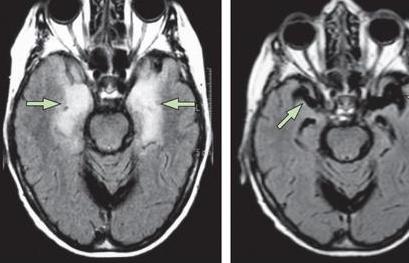

脑炎后遗症的出现对于患者的影响是很大的,对于每位脑炎后遗症患者来说,及时的接受正规专业的治疗是很关键的,也是很重要的,目前,治疗脑炎后遗症的方法是很多的,常见的方法包括免疫疗法、推拿疗法、对症治疗以及抗病毒治疗,这几种治疗方法的效果都是很不错的,下面我们就来进行一下详细的介绍,希望可以帮到大家。